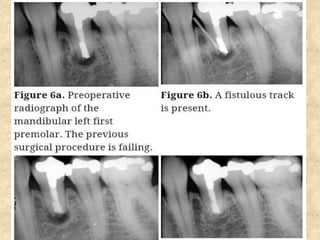

7. Repair of perforation:

• Repairing requires a material that should be biocompatible, should

withstand moisture without dissolving and should have good sealing

ability.

• MTA was used for treatment of perforation that caused by an iatrogenic

causes or complication of internal resorption.

• Procedure is done under anesthesia and rubber dam.

• After performing access opening, the canals are irrigated with NaOCl.

• Calcium hydroxide can be placed in the canal in between appointments

which will help control hemorrhage.

• Before placing MTA, calcium hydroxide should be completely removed.

• The apical portion of the canal is obturated with sectional cone

technique using gutta percha and root canal sealer.

• MTA is placed into the defect and moist cotton pellet is placed over it.

The access cavity is closed with a temporary restoration.

• The remaining portion of the canal is restored with a permanent filling

material after at least 3-4 hours.

Steps involved in the repair of perforation: